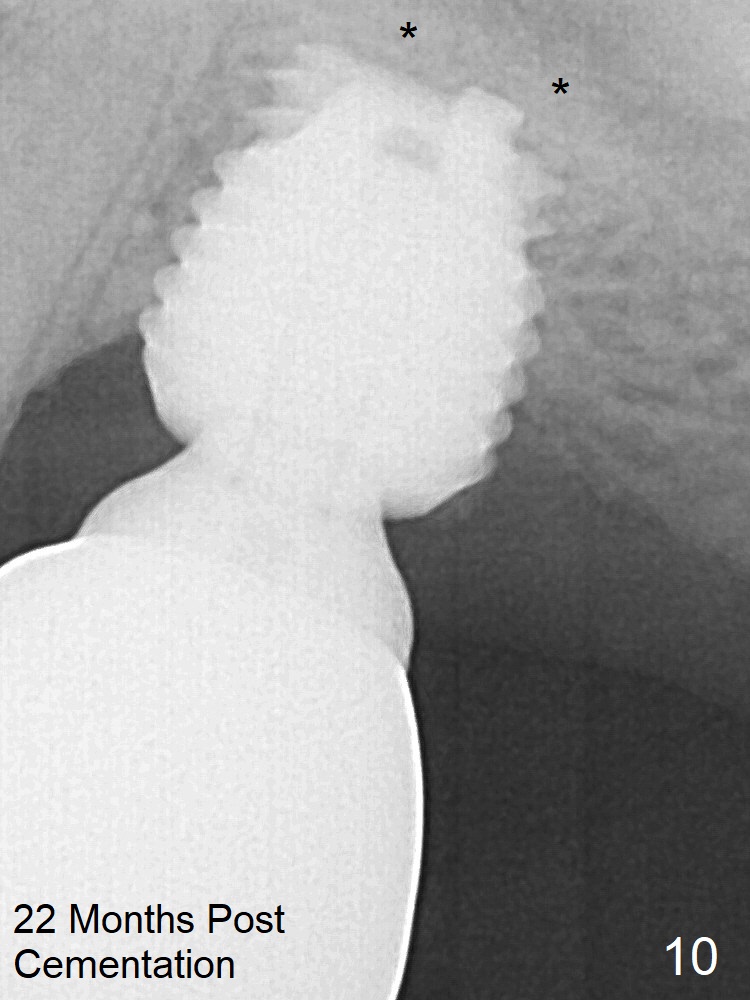

When the patient returns for impression 6.5 months postop, the provisional has dislodged because of the short abutment (Fig.7 A (6.5x4(2) mm). A longer one is placed (6.5x5(3) mm). The original sinus floor has been resorbed, while there is bone formation apical to the implant (*). Two distal threads are not covered by the bone. Therefore the implant should have been placed higher. There is a distinct layer of bone apical to the implant 22 months post cementation (Fig.10 *). The implant remains infection free 3 years 10 months post cementation (Fig.12) due to the thick gingiva and good oral hygiene.